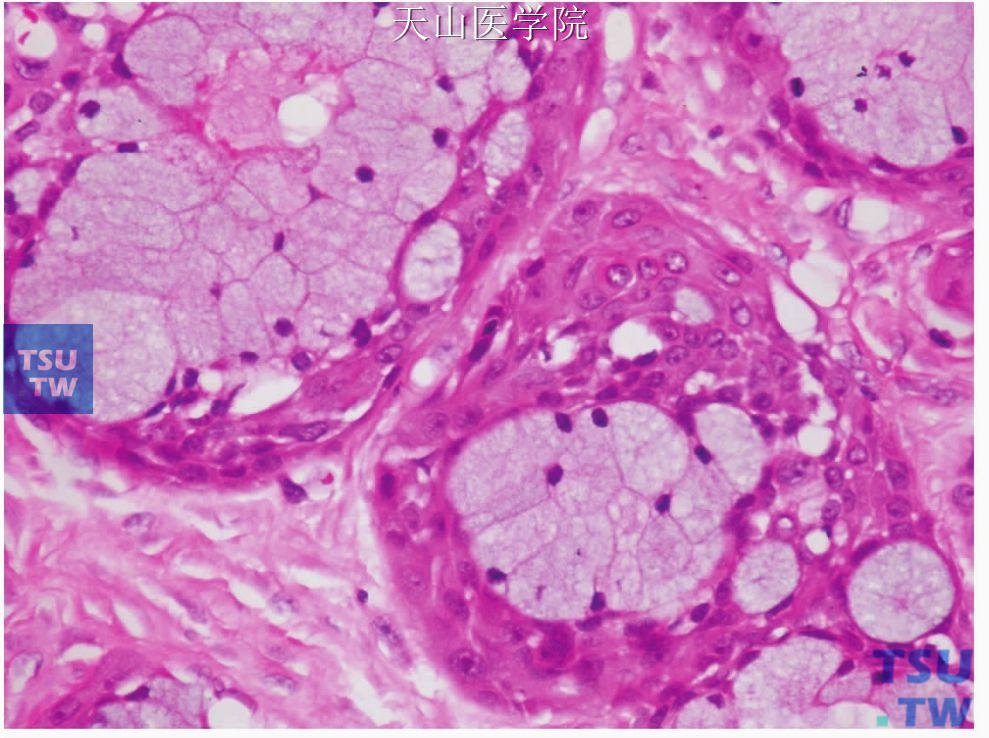

黏液表皮样癌(mucoepidermoid carcinoma,MEC)是由不同比例的黏液细胞、中间细胞、表皮样细胞构成的恶性肿瘤。有时含有柱状细胞、透明细胞偶尔还有嗜酸细胞,常呈囊性生长。黏液

黏液表皮样癌(mucoepidermoid carcinoma)的细胞涂片可以看到如病理组织切片中所见到的三种细胞类型:黏液细胞、表皮样细胞和中间细胞。黏液细胞呈圆形或卵圆形,细胞核小,居中或偏